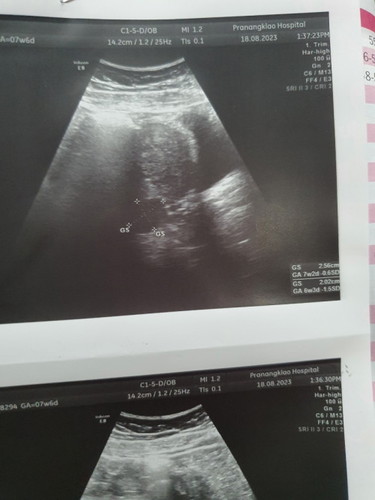

อัลตร้าซาวด์ไม่เจอตัวอ่อน

ตรวจครรภ์เเล้วพบว่าตั้งครรภ์เลยไปหาคุณหมอ คุณหมออัลตร้าซาวด์ให้ไม่พบอะไรเลย ผ่านไป1เดือนซาวด์อีกรอบพบเเค่ถุงตั้งครรภ์ เสี่ยงท้องลมมั๊ยคะ

ไข่อาจตกช้าคะ รออีกสัก2-3วีค อาจเจอน้องคะ